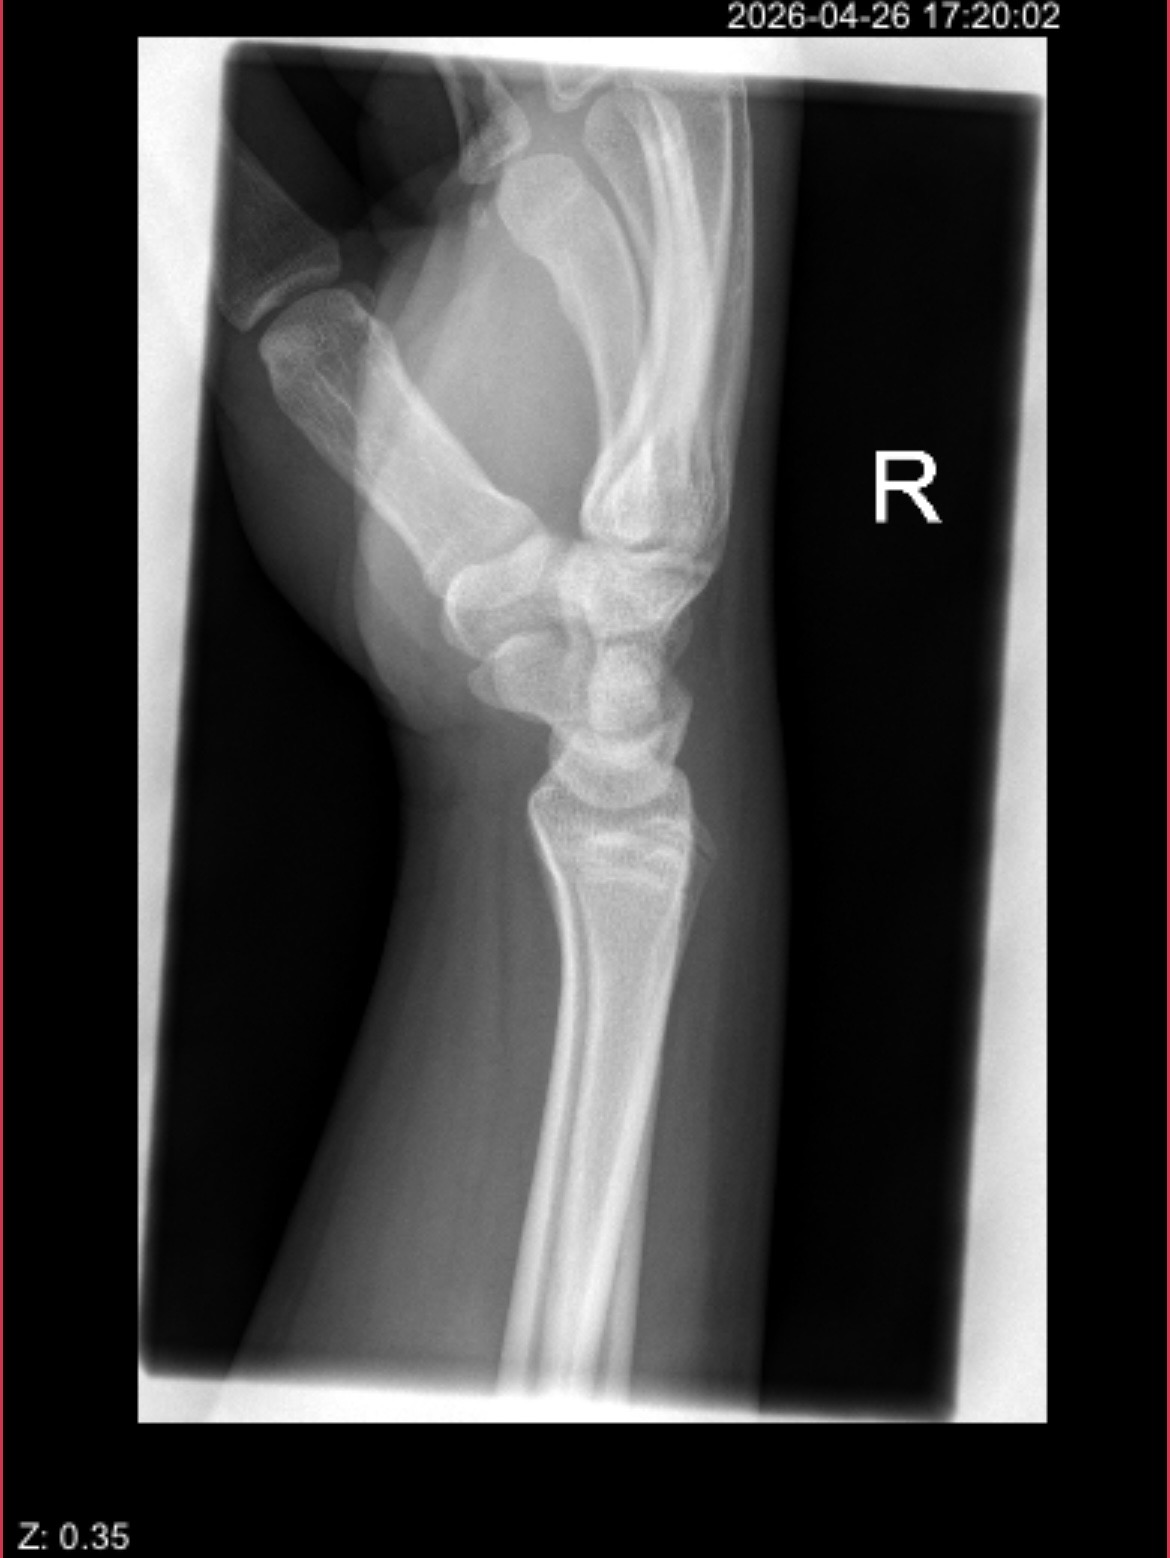

i'm not a doctor or sum shit but they dont look fully fusedAre my growth plates still open????

How much i have to grow you think?Its almost over